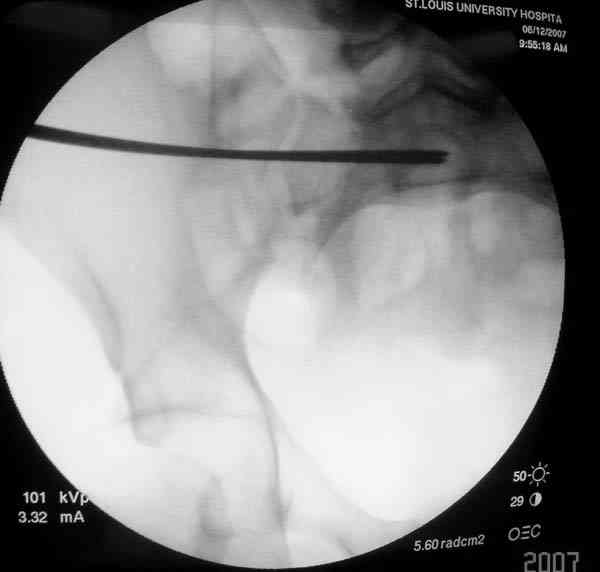

Применение длинных (7 мм каннюлированных, с резбой на всем протяжении

от компании Mercury) шурупов, проведенных между двумя илиосакральными

сочленениями нейтрализирует деформацию до наступления сращения.

На другом конце затягивание гайкой создает эффект болта-стяжки.

Сверло-направитель в 3.2 мм проводится вручную без применения дрели, и

длина в 46 см обычно достаточна до захвата следующего

илио-сактрального сочленения.

Проведение сверла под неврологическим мониторингом уменьшает риск

повреждения нервов во время операции.

Имя     : SI screw placement.jpg

Тип     : image/jpeg

Размер  : 25003 байтов

Описание: отсутствует

Url     : http://weborto.net:8080/pipermail/ortho/attachments/20070619/660e38d0/attachment-0005.jpg